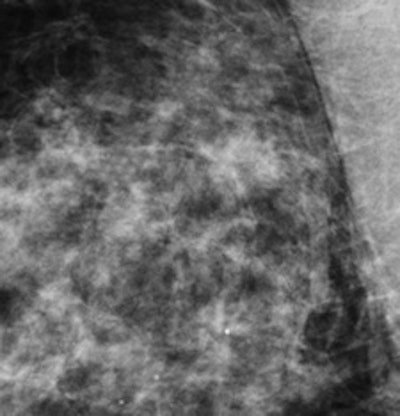

Example of improved screening with 3D imaging with tomosynthesis -- a cancer stellate opacity with distortion with tomosynthesis (right) and with standard mammography (left)."We found that tomosynthesis as a triage in recalled cases reduced [recall rates] and did not cause any false-negative recommendations," the researchers concluded.